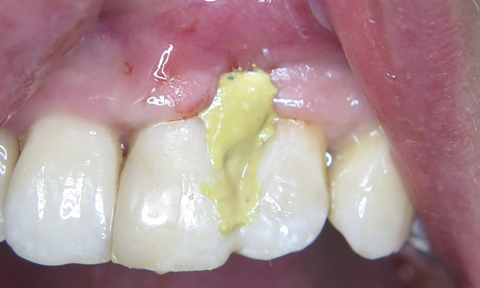

Тому, після загоєння та витримки строків біодеградації кісткового матеріалу (через 4 місяці) прийнято рішення про проведення естетичної корекції ділянки ясеневого сосочка. Під інфільтраційною анестезією проведено косий розріз на 1.5 – 2 мм вище septa interalveolaria. За допомогою мікрохірургічного распатора TKN2SX (Hu-Friedy) сформовано кисет. З ділянки горба верхньої щелепи (за методикою книжки) отримано сполучнотканинний трансплантат. Поверхні коренів зуба 21 та 22 очищено та згладжено за допомогою пародонтальних кюрет. Підготовлену поверхню кореня обробили доксицикліном (фото 11).

Препарат змили розчином Perio aid 0.12%. З приводу необхідності хімічної обробки кореня зуба під час хірургічних втручань існує декілька точок зору. Ми вбачаємо в цій процедурі можливість додаткової антибактеріальної очистки та покращення візуального контролю перед накладанням швів. Трансплантат введено в реципієнтну ділянку (фото 12) та фіксовано модифікованим підвісним швом (див. схема 3, фото 13).